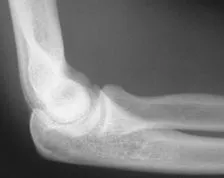

An X-ray is necessary to determine if there is a bone injury. X-rays can also help show the direction of the dislocation.

X-rays are the best way to confirm that the elbow is dislocated. If bone detail is difficult to identify on an X-ray, a computed tomography (CT) scan may be done. If it is important to evaluate the ligaments, a magnetic resonance image (MRI) can be helpful.

First, however, the doctor will set the elbow, without waiting for the CT scan or MRI. These studies are usually taken after the dislocated elbow has been put back in place.